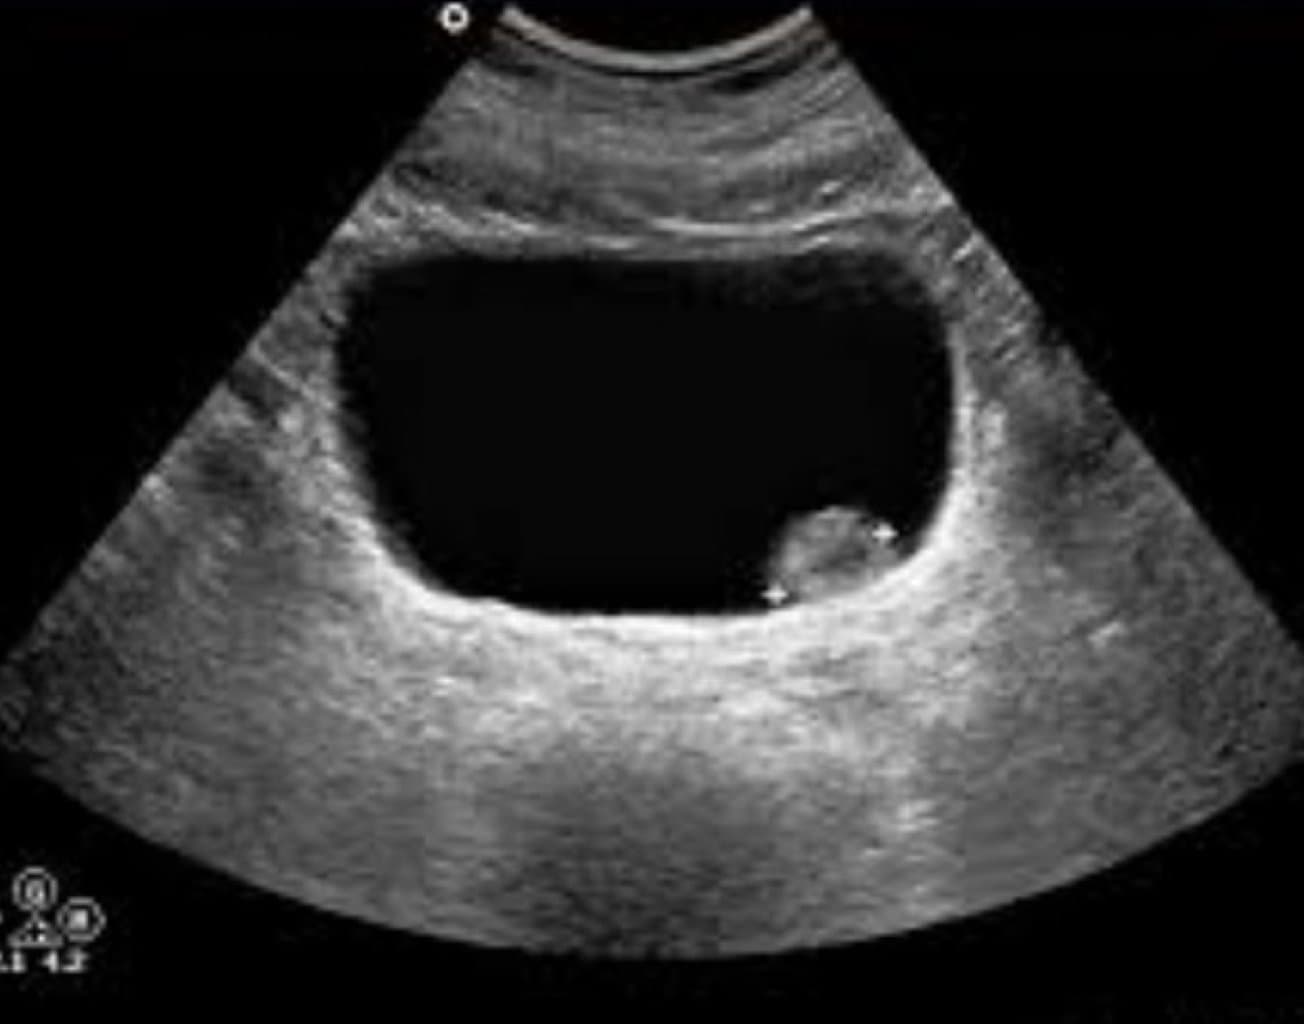

| İmaging (Görüntüləmə) | Xərçəngin mərhələsini müəyyən etmək üçün Ultrason, MRT və CT testlərindən istifadə olunur. |